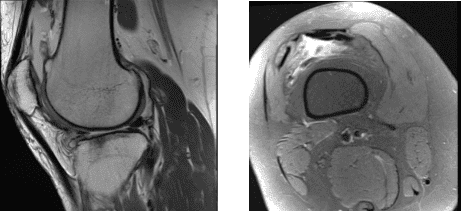

MRI were presented and found horizontal tear anterior horn and body lateral meniscus with intrasubstance meniscal cyst contiguous with the anterior 1 tear and edema in the anterior infrapatellar fat.

Lateral subluxation patella with patellofemoral arthrosis with Joint effusion with synovitis were observed. Also, her hamstring and gastrocnemius tendinopathy with medial bursitis.